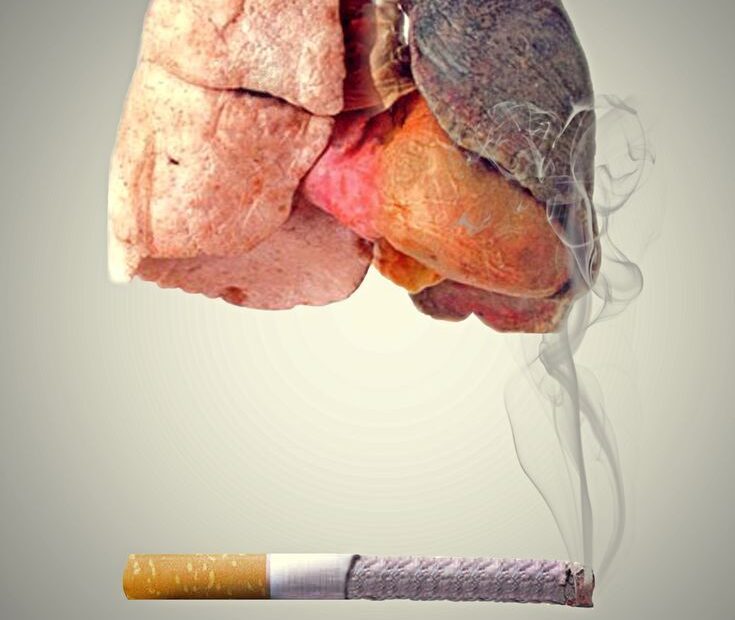

Dr. Silvana Sadria , Mjeke Pneumologe. Fibroza pulmonare idiopatike (IPF) është një sëmundje e rrallë e frymëmarrjes e karakterizuar nga depozitimi i indit lidhës ose “mbresë” në mushkëri; Në praktikë indi i shëndetshëm i mushkërive i cili është një ind elastik zëvendësohet nga indi i… Read More »Fibroza pulmonare idiopatike: Ç’farë është dhe si trajtohet?